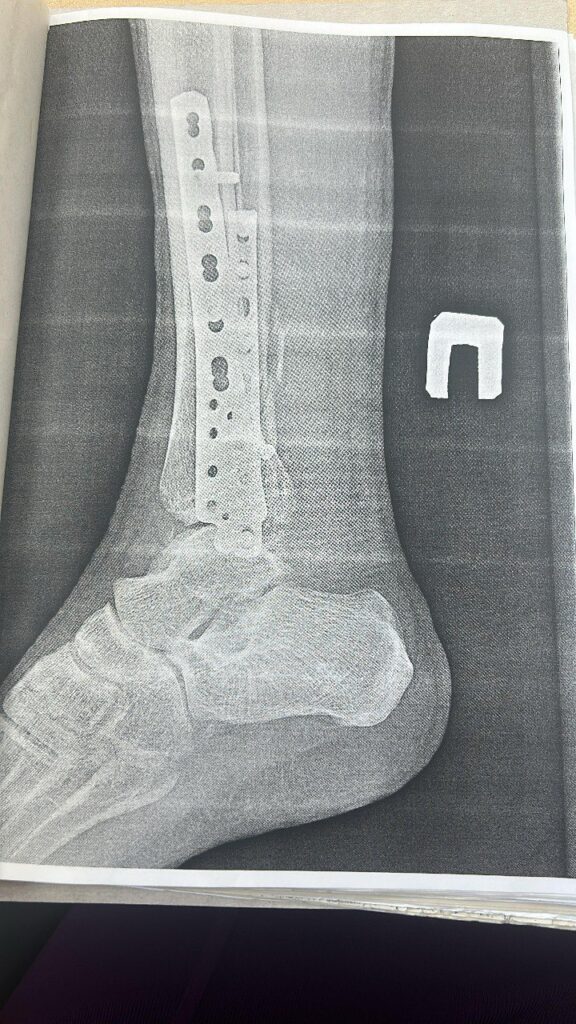

По информации Благовещенского городского суда, упавший возле подъезда на улице Комсомольской горожанин сломал обе лодыжки и вывихнул стопу. Ему пришлось лечь в больницу и долго восстанавливаться.